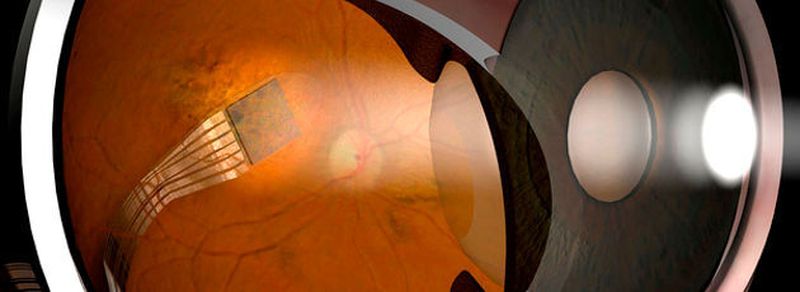

Etwa 300 erblindete Menschen weltweit können mit Hilfe eines Netzhaut-Chips im Auge wieder etwas sehen. Die Technik, die seit mehr als zehn Jahren angewendet wird, hilft Patienten mit der erblich bedingten Augenkrankheit Retinitis pigmentosa. Dabei sterben die Sehzellen ab, die in der Netzhaut Licht in elektrische Impulse umwandeln. In Deutschland leben etwa 30 000 bis 40 000 Menschen mit dieser Krankheit, wie Augenarzt Armin Scharrer sagt. Pro Jahr erblinden knapp 1000. Die noch teure Technik kann ihnen helfen – doch es gibt noch einiges zu verbessen. Darüber diskutieren von Donnerstag an Experten beim Internationalen Kongress der Deutschen Augenchirurgen in Nürnberg.

Das von Tübinger Forschern entwickelte deutsche Implantat (Alpha IMS) wird unter die Netzhaut gesetzt. Der drei mal drei Millimeter große Chip ersetzt dort die abgestorbenen lichtempfindlichen Sehzellen, die sogenannten Zapfen. Wie bei einem Kamera-Chip nehmen 1500 Fotodioden einfallendes Licht auf und wandeln es in elektrische Signale um. Diese werden über den Sehnerv ans Gehirn weitergegeben, wo dann wieder Bilder entstehen können. Das funktioniert bei etwa 75 Prozent der operierten Patienten. Die Technik kann nur bei Menschen genutzt werden, die einmal sehen konnten.

Für den Eingriff nötig sind ein Augenarzt und ein Neurochirurg. Denn das Energiemodul – die Batterie – wird am Hinterkopf unter die Haut gesetzt. Ein Kabel führt von dort zum Auge. „Das ist also wirklich eine komplizierte Sache“, sagt Scharrer. Alles in allem kostet die Behandlung rund 100.000 Euro. In Deutschland seien mittlerweile einige Krankenkassen bereit, die Kosten zu übernehmen.

Die US-Technik (Argus II) hat im Gegensatz zur deutschen nur 60 Elektroden und liefert damit kein so gutes Bild, wie Scharrer sagt. Dafür ist die OP deutlich unkomplizierter: Der Patient trägt hier eine Brille mit einer Kamera. Die Bild-Signale werden drahtlos an den Chip im Auge übertragen, der nicht unter, sondern auf der Netzhaut sitzt. Auch die Batterie wird nicht implantiert, sondern steckt in einem Kästchen in der Tasche.